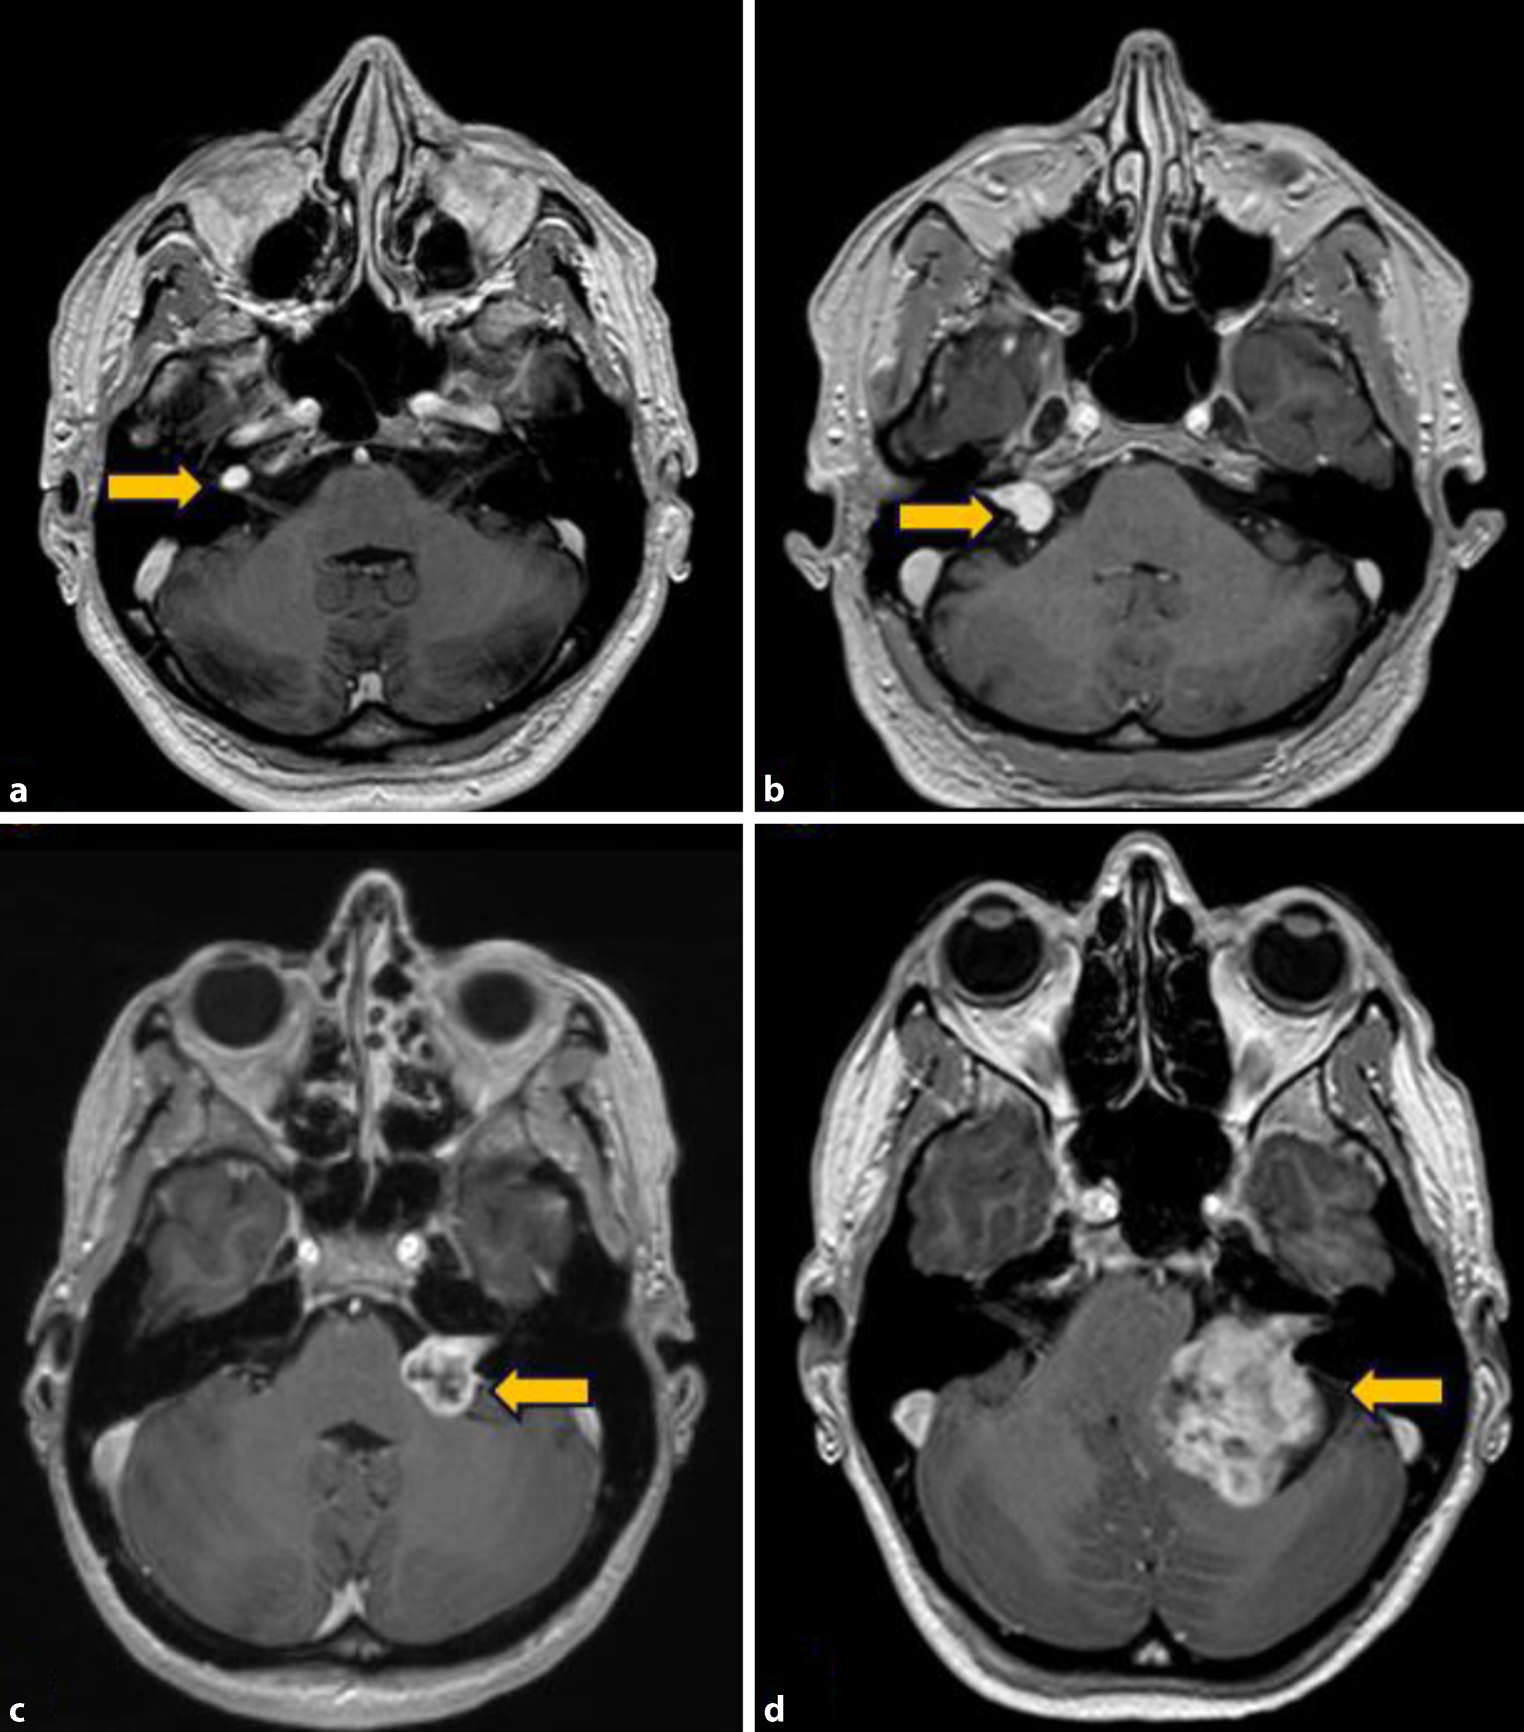

MRT, Ton- und Sprachaudiometrie, Vestibularis-Diagnostik und Erhebung der Fazialisfunktion sind die wesentlichen Untersuchungen zur Abklärung eines VS. Die Bildgebung mittels MRT ist heute die Methode der 1. Wahl für die Diagnose- und Verlaufsbeurteilung, wobei spezielle Sequenzprotokolle angewendet werden. Mithilfe der Bildgebung wird das VS klassifiziert. Ein häufig verwendeter, internationaler Standard zur Tumoreinteilung ist die Koos-Klassifikation, welche die VS nach anatomischer Lage und Tumorgröße graduiert (Grad I–IV, Tab. 1, Abb. 1). Intralabyrinthäre VS (Lage z. B. in Cochlea, Vestibulum, Bogengängen) werden als separate Entität gewertet.

MRT Darstellungen von VS Patienten – Repräsentation von allen KOOS Graden, a KOOS°I, b KOOS°II, c KOOS°III, d KOOS°IV